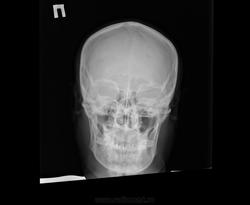

Помогите, пожалуйста, с описанием снимка черепа https://radiomed.ru/sites/default/files/styles/case_slider_image/public/user/19361/ffe4984c7ada4fa089e1ecdd63211bcf_1.jpg?itok=ycAIFYVP ID:46704 Mon, 21/04/2014 - 12:41 #1 Nela Offline Last seen: 6 years 4 months ago Joined: 12.05.2009 - 20:43 Posts: 1847 Норма Mon, 21/04/2014 - 18:44 #2 largooowinch Offline Last seen: 10 years 3 months ago Joined: 29.10.2013 - 22:07 Posts: 65 я за норму Mon, 21/04/2014 - 21:46 #3 Дмитрий Волегов Offline Last seen: 3 years 9 months ago Joined: 22.05.2013 - 00:32 Posts: 1148 Турецкого седла мне не видно. Предложил бы переснять. С Уважением, Дмитрий. Mon, 21/04/2014 - 23:46 #4 OPEXOB Offline Last seen: 10 years 2 months ago Joined: 26.07.2008 - 10:02 Posts: 280 Ужасная укладка - лаборанту по рукам линейкой ! Wed, 30/04/2014 - 10:55 #5 Доктор Ре. Offline Last seen: 10 years 5 months ago Joined: 15.04.2014 - 16:37 Posts: 129 На мой взгляд имеется некоторое уплощение в переднезаднем направлении и форма черепа по типу конической. Может ли здесь быть акроцефалия?

Норма

я за норму

Ужасная укладка - лаборанту по рукам линейкой !

На мой взгляд имеется некоторое уплощение в переднезаднем направлении и форма черепа по типу конической. Может ли здесь быть акроцефалия?